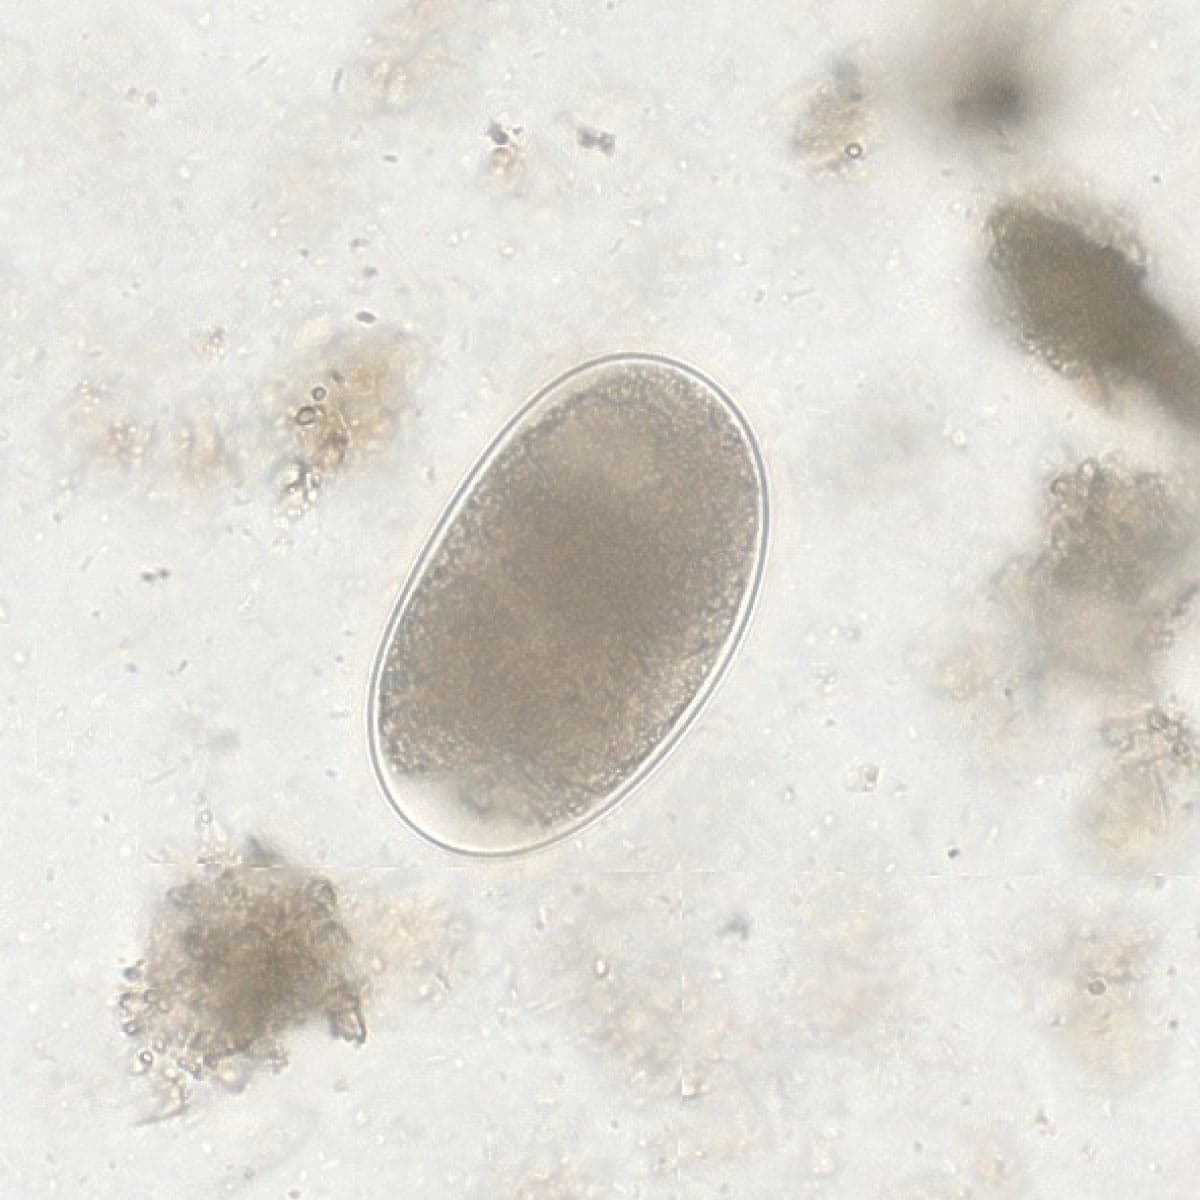

Automatic detection over 30 species

Built on worldwide parasite-positive specimens, ParaScout AI identifies a vast number of parasite species, including those that are clinically rare or challenging to find.

Evidence of results detection

Visual evidence is provided for every diagnosis.